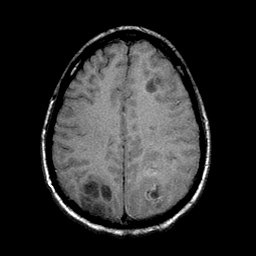

Sarcoma, MR Study #1 mr-t1 -- Slice #17

[Home][Help][Clinical] Slice 17